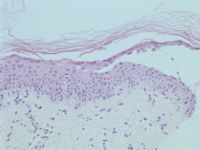

De diagnose wordt gesteld op klinisch beeld, histologie, en immunofluorescentie. Er is blaarvorming (acantholyse) hoog in de epidermis en daar is ook de immunofluorescentie het sterkst. De IgG antistoffen zijn gericht tegen desmogleïne 1, een 160 kd eiwit dat vooral voorkomt in het stratum granulosum. Bij paraneoplastische pemphigus zijn er ook antistoffen gericht tegen desmogleïne 3, en dat veroorzaakt diepere schade en slijmvliesbetrokkenheid.

Histologie pemphigus foliaceus

ingescande coupe (zoom)

Bron hoge resolutie PA-foto: Kevin Kwee en Afdeling Pathologie MUMC. Klik op de afbeelding om in te zoomen.